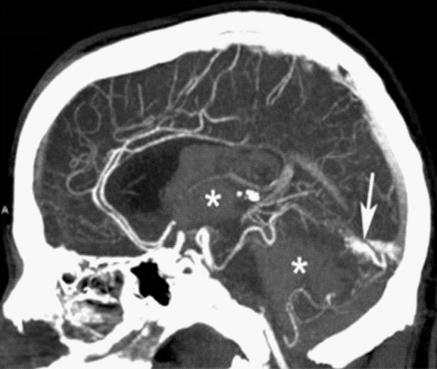

CTA of a vascular malformation with intraventricular hemorrhage.

CTA can be used assess acute stroke patients by identifying clots in the arteries of the brain.[1] It can also be used to identify small aneurysms or arteriovenous malformation inside the brain that can be life-threatening. While CTA can produce high quality images of the carotid arteries for grading the level of stenosis (narrowing of the vessel), calcium deposits (calcified plaques) in the area where the vessels split can lead to interference with accurate stenosis grading. Because of this, magnetic resonance angiography is used more often for this purpose.[2]